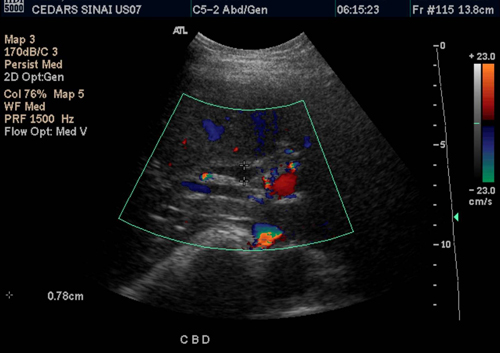

A whole abdomen ultrasound is a powerful diagnostic tool that provides a comprehensive view of the abdomen, including the liver, gallbladder, pancreas, kidneys, and more. For women like Kavita, it means more than just a medical procedure; it’s a gateway to understanding and addressing the silent whispers of their bodies, often ignored amidst daily responsibilities.